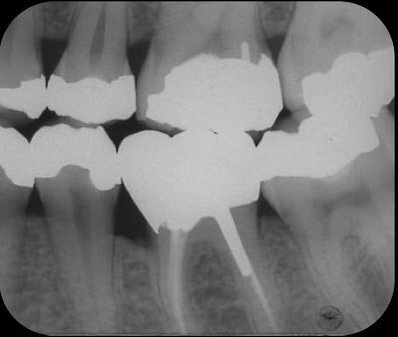

Als jonge tandarts was ik volkomen ontdaan over deze iatrogene complicatie. Er waren in 1982 geen speciale cementen beschikbaar om een perforatie te sluiten, en dus besloot ik om het defect tijdelijk af te sluiten met amalgaam. De twee mesiale en twee distale kanalen werden met handvijlen geprepareerd, en de kanalen werden geïrrigeerd met 2,5% natriumhypochloriet. Daarna vulde ik de kanalen door middel van laterale condensatie met gutta-percha en AH26, waarbij in het distolinguale kanaal ruimte werd gemaakt voor een wortelstift (afb. 3). Volgens de toen geldende inzichten was een gegoten opbouw geïndiceerd alvorens er een volledige gouden kroon geplaatst zou worden.

Het plan was om de perforatie, die deels subcrestaal lag, op te nemen in de outline van de kroon (afb. 4). In een daaropvolgende zitting deed ik aan de mesiale zijde van de 36 een kroonverlenging, met als doel om het perforatieoppervlak supracrestaal te brengen, en zo beter toegankelijk te maken voor een volledige omslijping met een schouderbevelpreparatie. De wondgenezing verliep ongestoord en de patiënt kreeg instructie over de interdentale reiniging van het behandelde gebied. Een maand later werd met behulp van een edelmetalen wortelstift (afb. 5) een Duralay opbouw gemaakt, die vervolgens werd aangegoten tot een edelmetalen stiftopbouw en geplaatst werd met zinkfosfaat cement. Weer drie weken later werd de volledige gouden kroon gecementeerd met zinkfosfaat cement (afb. 6). De patiënt kon de interdentale ruimte uitstekend schoonhouden met ragers.

Afb. 3: Kanaalvulling aanbracht en perforatie afgesloten met amalgaam

Afb. 4: Bitewing waarop lokalisatie en omvang van de perforatie zichtbaar zijn